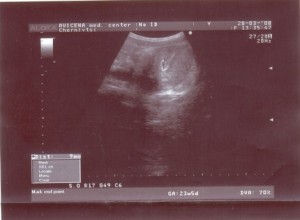

Узі на 3 тижні вагітності

Більшість домашніх тестів при зачатті природним шляхом можуть давати негативні результати, проте 3 тиждень вагітності може бути з легкістю визначена в клінічних умовах. У цей період відбувається запліднення. УЗД заданого триместру вже здатне показати вам ембріон, незалежно від способу зачаття.

Саме в цей період після зачаття відбувається активний розподіл ембріона, яке є на даному терміні становий активністю. В процесі розвиваючого поділу, відбувається переміщення ембріона в порожнину матки. По досягненню кінцевої мети, здійснюється закріплення плоду на стінках, що дозволяє почати повномасштабне розвиток (закріплення підтверджується по УЗД).

Основним методом діагностики заданого триместру є УЗД (в тому числі і після ЕКЗ). Після зачаття, ембріон є сферою 2 до 5 мм. Таким чином, завдяки УЗД перший триместр може бути проведено під повним контролем.